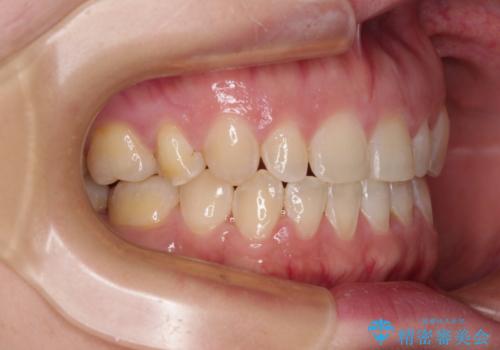

隙間の空いた歯列とボロボロの乳歯 インプラント治療と矯正治療

- 隙間の多い歯列や傾斜した奥歯、むし歯の酷い残存乳歯を気にして来院された患者様です。

傾斜した下顎の奥歯は、矯正治療にてまずは歯軸を改善させ、隙間が閉じられるようであればそのままに、閉じられないようであればインプラント治療を行うこととしました。

上顎のむし歯の酷い残存乳歯は抜歯をし、矯正治療の途中でインプラントを埋入、矯正治療後に補綴治療を行うこととしました。